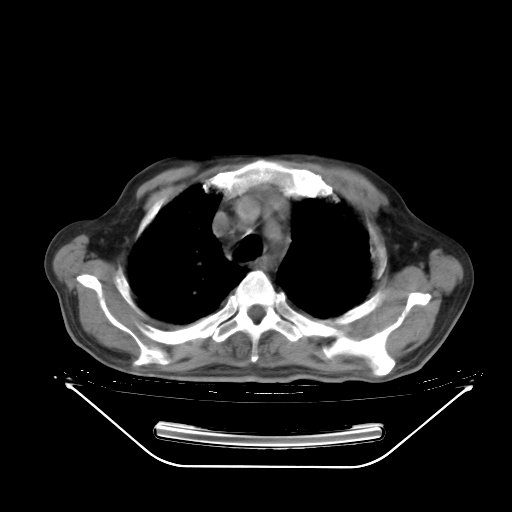

今天复查肺部CT,发现双肺广泛磨玻璃样改变。所以我把3月19日和5月9日相隔50天的肺部CT上传。请大家会诊。

2009年3月19日肺部CT片。

2009年3月19日肺部CT